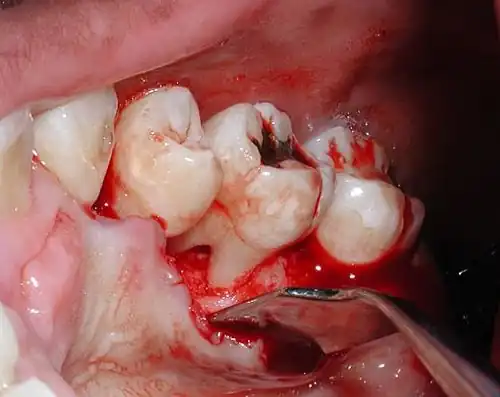

Furcation defect

In dentistry, a furcation defect is bone loss, usually a result of periodontal disease, affecting the base of the root trunk of a tooth where two or more roots meet (bifurcation or trifurcation). The extent and configuration of the defect are factors in both diagnosis and treatment planning.[1]

Diagnosis

Nabers probe is used to check for furcation involvement clinically. Recently, cone beam computerised technology (CBCT) has also be used to detect furcation.[5] Periapical and interproximal intraoral radiographs can help diagnosing and locating the furcation.